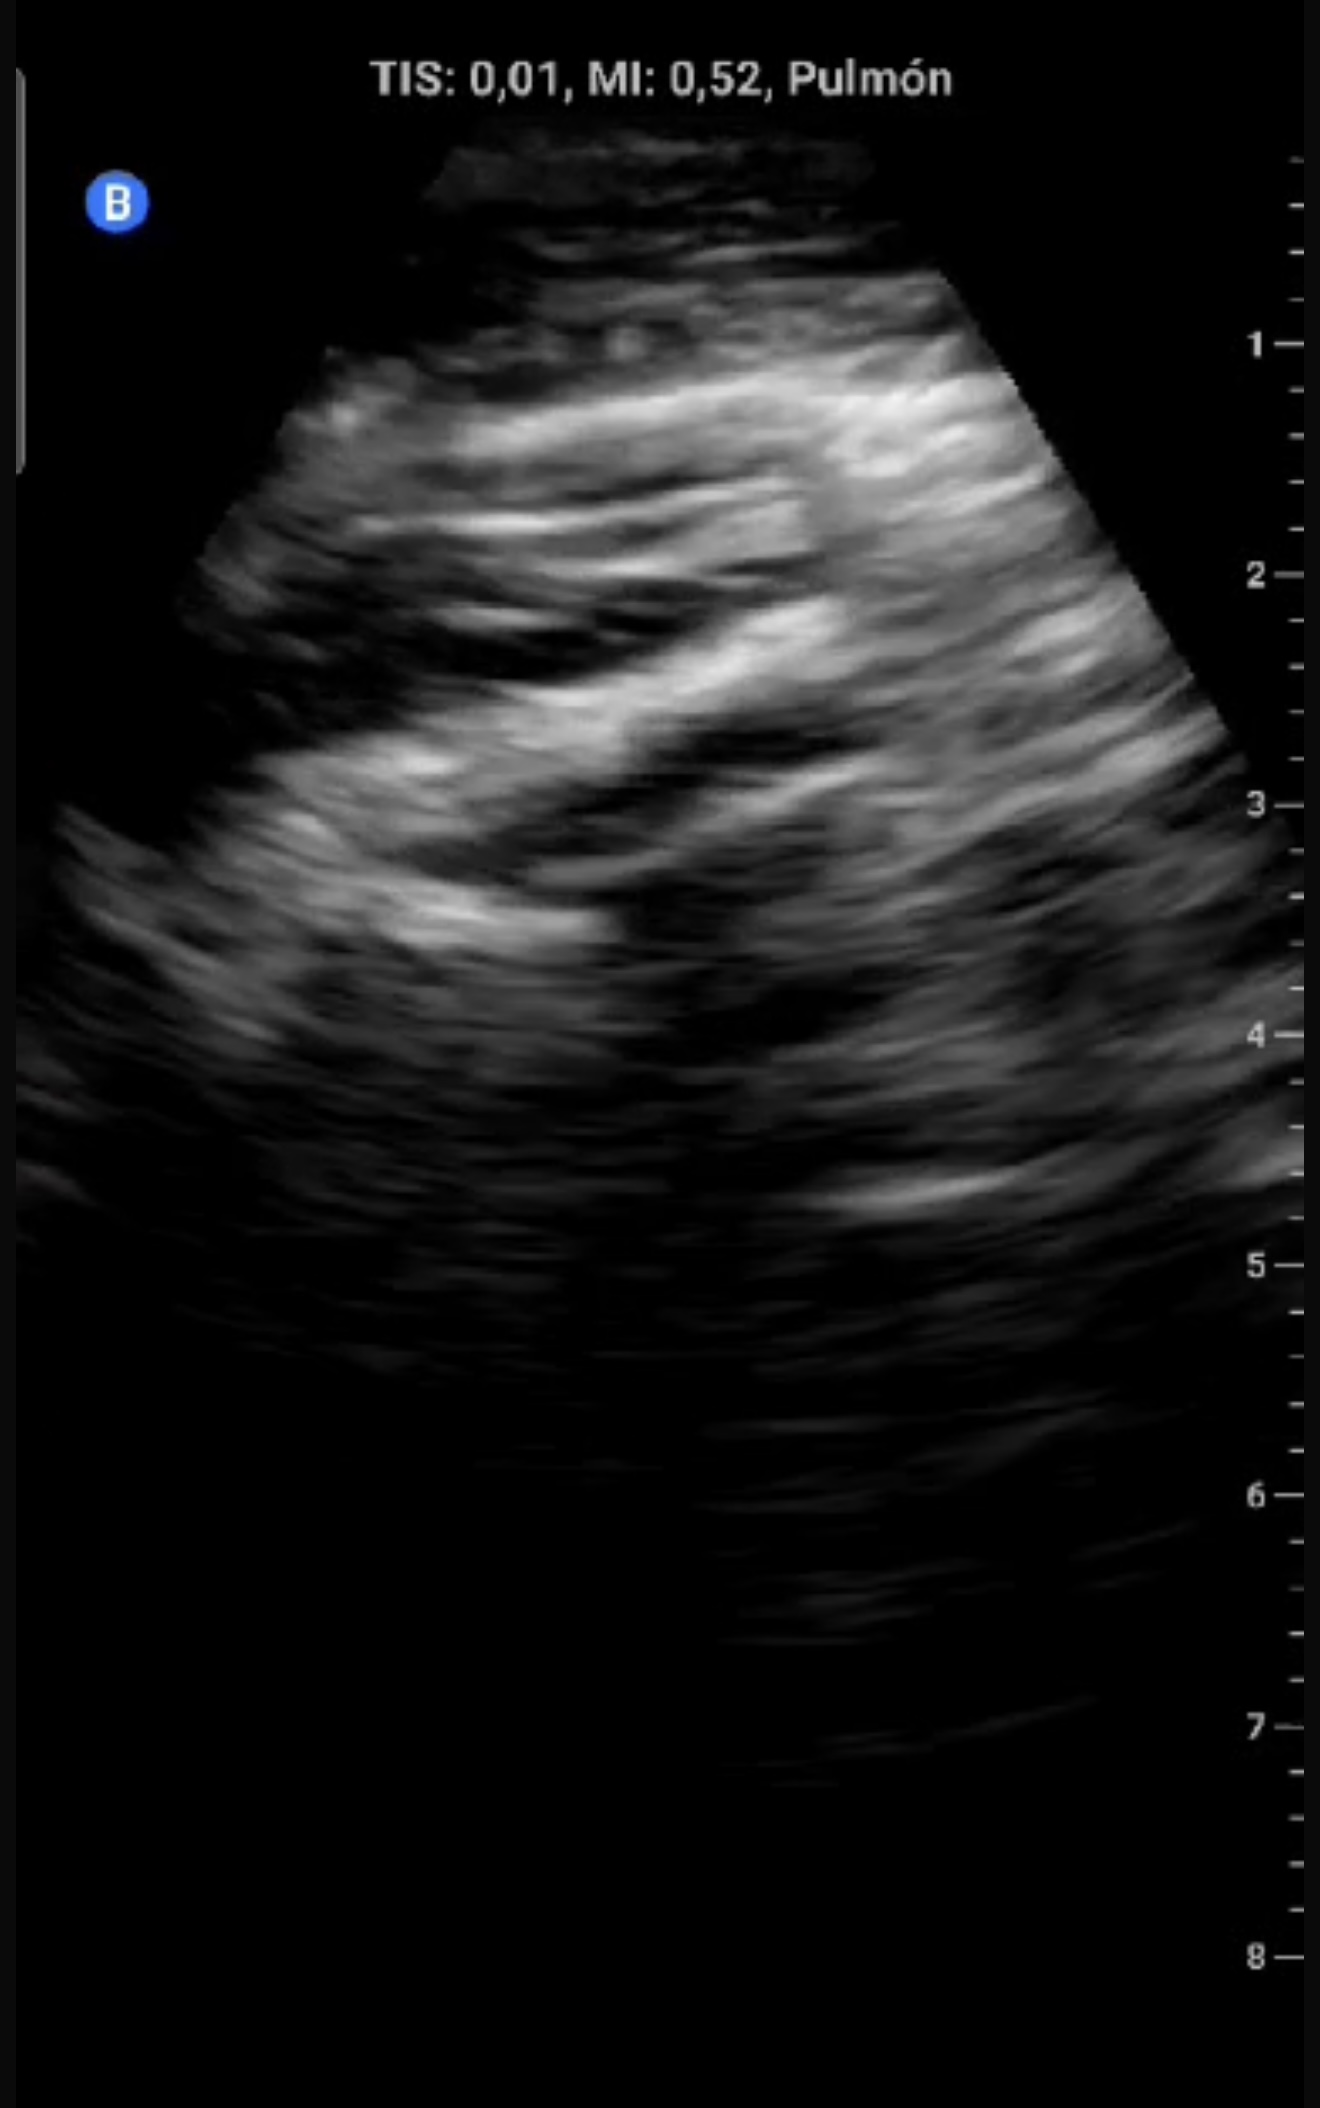

Eco clínica:

Ausencia de deslizamiento pleural (línea pleural fija), sugiriendo neumotórax.

Descripción de los hallazgos ecográficos

En modo B, ausencia de deslizamiento pleural con línea pleural estática hiperecoica. En modo M, signo de code bar (ausencia del signo de la playa).